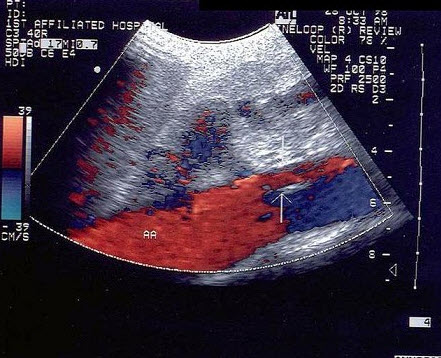

18、单项选择题

某患者左肾超声声像图如下,最可能的诊断为()